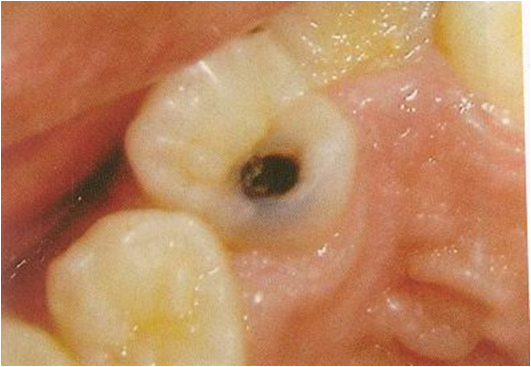

Pit and Fissure caries

- Highest prevalence of all caries bacteria rapidly colonize the pits and fissures of the newly erupted teeth

- Shape, morphological variation and depth of pit and fissures contributes to their high susceptibility to caries.

- Caries expand as it penetrates in to the enamel.

- Entry site may appear much smaller than actual lesion, making clinical diagnosis difficult.

- Carious lesion of pits and fissures develop from attack on their walls.

- In cross section, the gross appearance of pit and fissure lesion is inverted V with a narrow entrance and a progressively wider area of involvement closer to the DEJ.